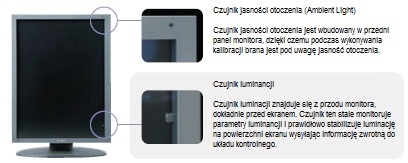

System stabilizacji podświetlania λ-Sentinel II

System stabilizacji podświetlenia λ-Sentinel II składa się z czujnika luminacji i układu kontrolującego luminację. Czujnik luminacji znajduje się z przodu monitora, dokładnie przed ekranem. Czujnik ten stale monitoruje panujące oświetlenie i prawidłowo ustala luminację ekranu wysyłając informację o oświetleniu zewnętrznym do układu kontrolnego. Dodatkowo, w monitorach serii i2, czujnik luminancji służy również jako wbudowany kalibrator, umożliwiając szybkie i proste wykonanie kalibracji monitora bez konieczności przykładania do monitora kalibratora zewnętrznego.

System stabilizacji podświetlenia λ-Sentinel II składa się z czujnika luminacji i układu kontrolującego luminację. Czujnik luminacji znajduje się z przodu monitora, dokładnie przed ekranem. Czujnik ten stale monitoruje panujące oświetlenie i prawidłowo ustala luminację ekranu wysyłając informację o oświetleniu zewnętrznym do układu kontrolnego. Dodatkowo, w monitorach serii i2, czujnik luminancji służy również jako wbudowany kalibrator, umożliwiając szybkie i proste wykonanie kalibracji monitora bez konieczności przykładania do monitora kalibratora zewnętrznego.